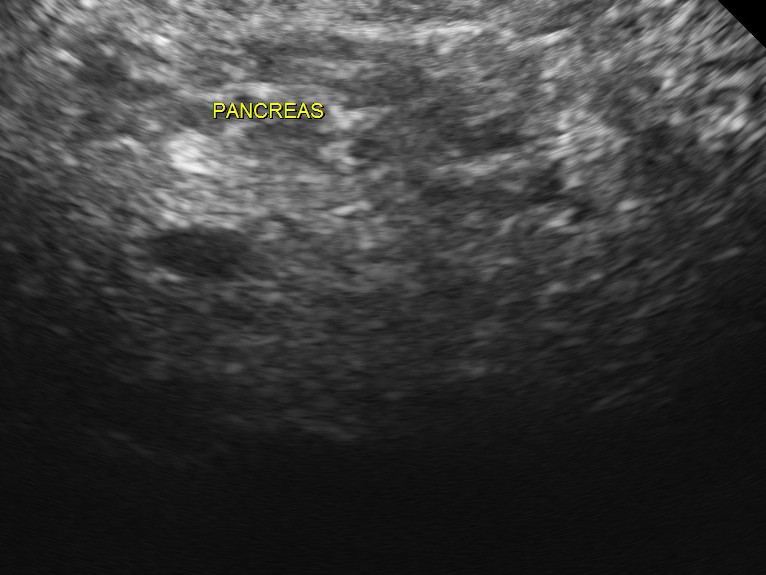

The following pictures were obtained.

The scan was otherwise normal.